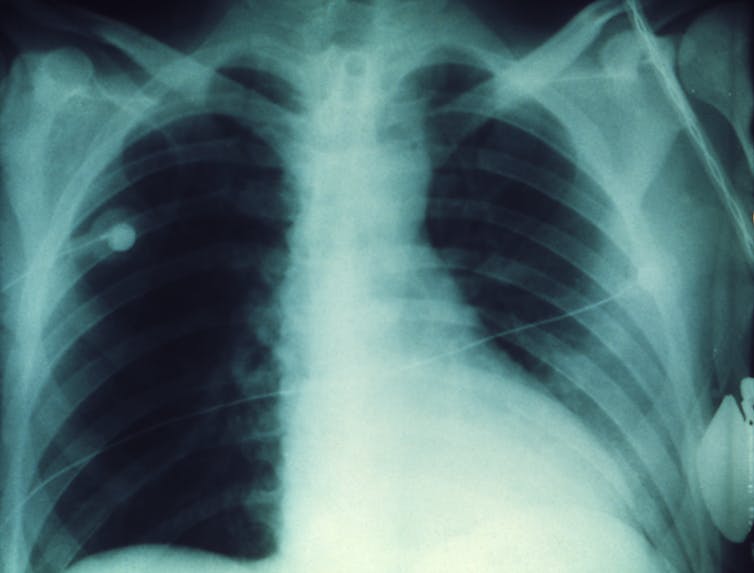

Легочная форма сибирской язвы фото - найдено 30 изображений